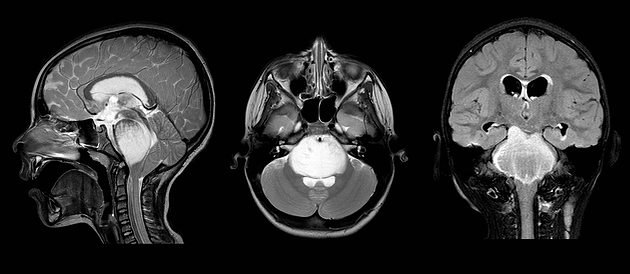

• MRI: An MRI can better distinguish between tumor, tumor-related swelling and normal tissue. The typical MRI appearance of a Diffuse Pontine Glioma is a round mass that expands the pons. When intravenous dye is administered, it displays a ring of enhancement. There can be growth up or down the brainstem, called axial growth, or growth forward or backward out of the brainstem, called exophytic growth.

• magnetic resonance imaging (MRI) - a diagnostic procedure that uses a combination of large magnets, radiofrequencies, and a computer to produce detailed images of organs and structures within the body. MRI provides greater anatomical detail than CT scan and can better distinguish between tumor, tumor-related swelling and normal tissue. The typical MRI appearance of a diffuse pontine glioma is a round mass that expands the pons. When intravenous dye is administered, it displays a ring of enhancement. There can be growth up or down the brainstem, axial growth, or growth forward or backward out of the brainstem, exophytic growth.